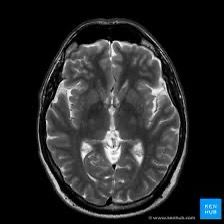

MRI Brain uses magnetic fields to create detailed images of the brain. It helps detect tumors, strokes magnetic field gradients.